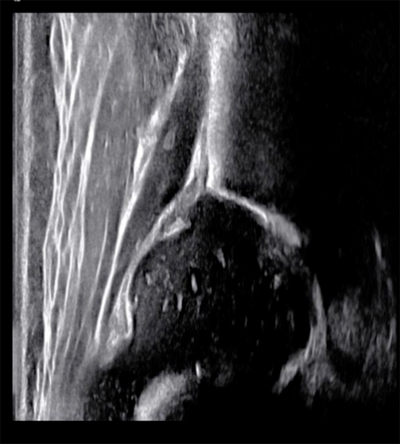

国内外专家一致认为超声是DDH早期(0-6月)筛查首选影像方法,应尽早进行超声筛查,推荐不晚于出生后第六周检查。超声检查中广泛应用Graf法:奥地利Graf教授开创的DDH超声检查法——通过判断髋臼形态,股骨头与髋臼的位置关系及测量α、β角度将髋关节分为四大类型及九个亚型。Graf法具有操作标准化、可定量等优点,其核心优势在于对骨性髋臼顶及软骨性髋臼顶进行了量化,从而客观评估髋关节发育情况。

正常婴幼儿髋关节超声影像

结合临床查体及超声诊断结果,就可确诊。超声能够准确评估髋关节形态,并给出具体的角度,从而对髋关节的发育进行分类,临床医生也根据此分类制定相应的治疗策略;另一方面,超声也能够评估治疗过程中股骨头的复位情况,一定程度可以预测患儿的预后。